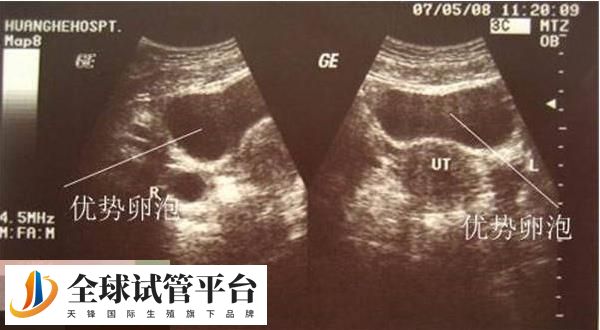

是可以进行促排卵的,25个基础卵泡也表明这多囊卵巢,那么其中就存在这一些治疗不好的卵泡。做试管促排卵是为了能够取出多颗卵子,便于受精卵的培育形成胚胎,而受精卵的培育就需要质量好的卵子和精子,虽然25个基础卵泡属于偏多了,但只要选对促排方案,最终取出的卵子数量也是比较可观的。

QQivf:至于能促起来多少个,这个跟卵泡质量以及运用到的方案都是有关系的,有的人25个基础卵泡最终促排可以达到20个,但也有人可能只有5个,一般正常来讲的话,有25个卵泡促排卵后取出12-16个的是比较常见的,一般运用超长方案促排卵后的卵子会多些,但促排卵的时间就会比其他方案长。

做试管婴儿的促排卵方案有很多种,主要分为长方案、超长方案、短方案、拮抗剂方案、微刺激方案等,而要是有25个基础卵泡,那么就可以运用超长方案、拮抗剂方案和微刺激方案,因为这些方案是比较适合多囊卵巢的,毕竟25个基础卵泡就属于是多囊了,而促排方案的情况就有: